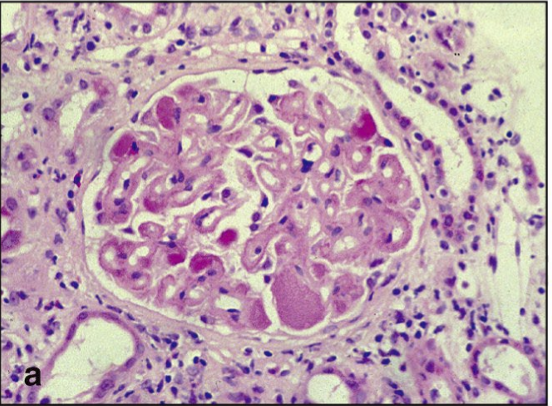

What condition is this from what disease

insulitis in T1D